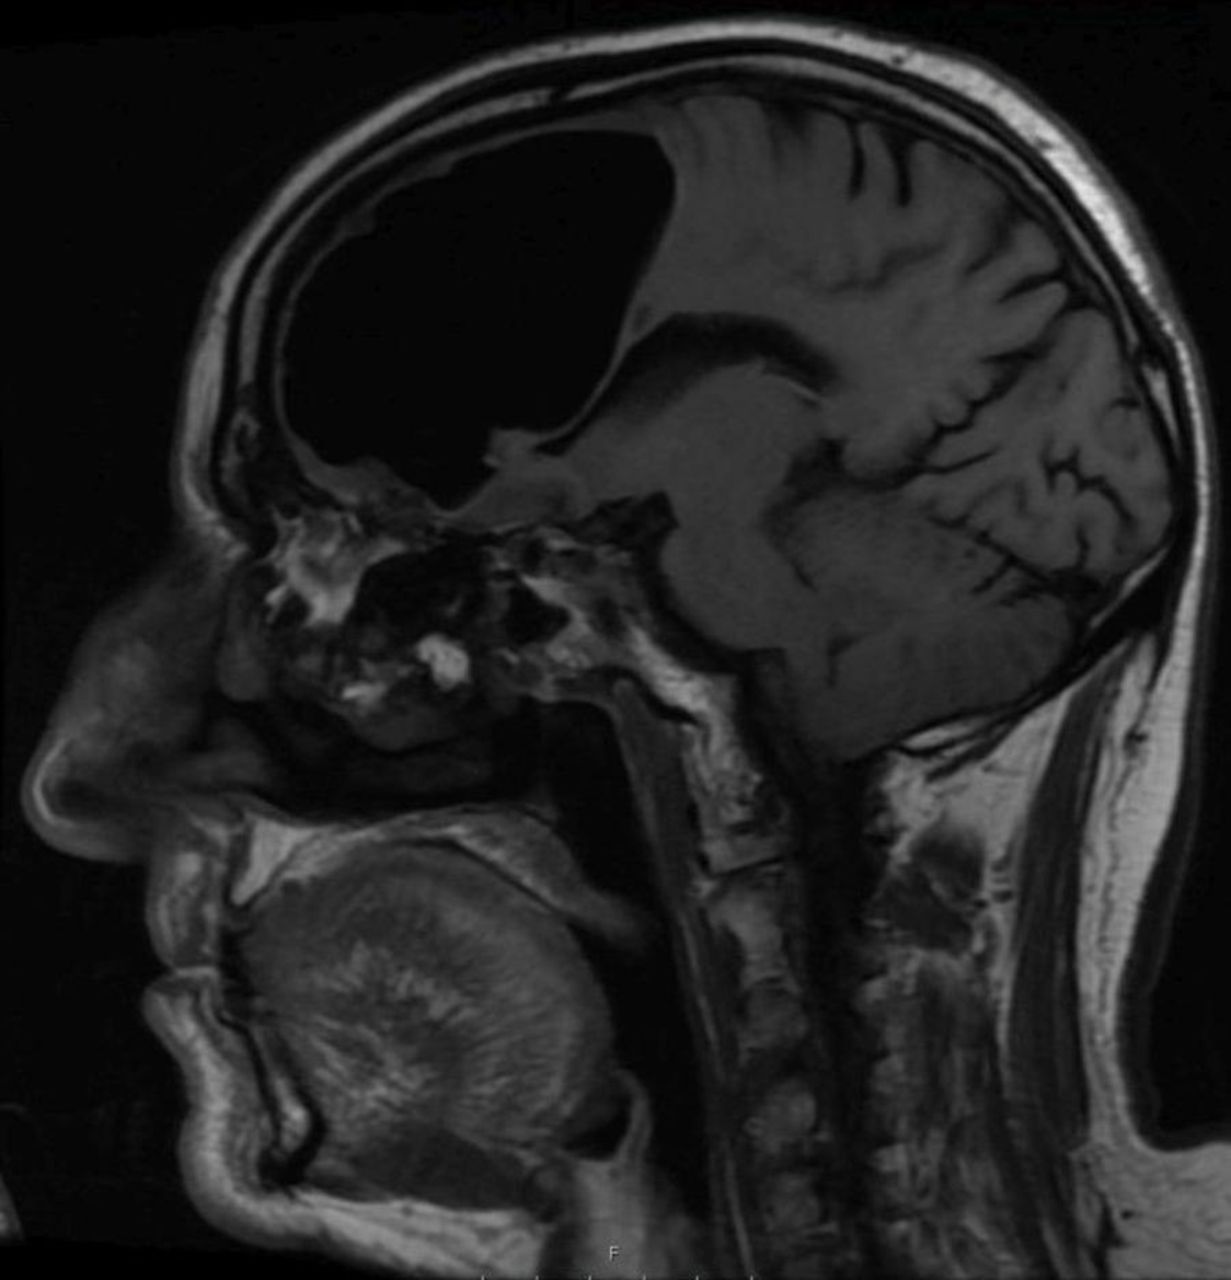

Na zdjęciach najlepiej widać, jak sporej części mózgu brakuje mężczyźnie

"Pustka" w głowie mężczyzny była szczególnie zaskakująca, ponieważ dolegliwości dotykające go wydawały się być czymś normalnym w jego wieku. Jednak poza słabością i problemami z równowagą, mężczyzna był w dobrej formie. Nie wykazywał zaburzenia mowy, widzenia, ani innych podstawowych funkcji życiowych.

Po dokładniejszym przebadaniu głowy 84-latka, lekarze znaleźli prawdopodobne źródło problemu. Według nich był to łagodny nowotwór kości. Lekarze sugerują, że guz utworzył mały otwór, przez który powietrze dostało się do mózgu i nie było już w stanie się z niego wydostać. - Najprawdopodobniej stało się to podczas... kichnięcia - stawierdził Brown w rozmowie z Washington Post.